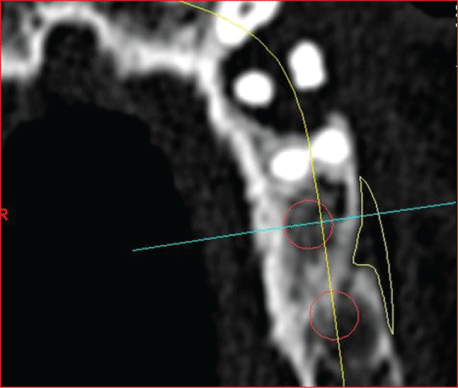

图1:异体骨块移植术后和开放刮牙术中的手术部位24和25。

先前准备的全瓣显示手术部位在牙齿24和25周围有明显的垂直骨缺损;第24颗牙仅靠顶端附着在骨头上。根据现有的再生措施的证据,由于患者的高度顺应性,缺损被异种骨(Bio - Oss collagen, Fa。Geistlich)广泛开放刮除(光滑根表面,在超声骨刀技术的帮助下完全去除肉芽组织;(图11和12)以及pregel™和Emdogain®(Straumann GmbH)的应用。然后用可吸收的膜覆盖填充的缺陷。

使用成骨螺钉(usstomp)将骨块固定到位,使用颗粒状异体替代材料(Puros Allograft Spongiosa Partikel[松质骨颗粒],Zimmer Dental GmbH, Munich)将小块不均匀的斑块平整(图1)。